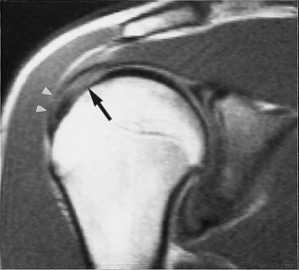

МРТ плечевого сустава. Т2-взвешенная корональная МРТ. Разрыв вращательной манжеты. Цветовая обработка изображения.

При МРТ плечевого сустава косвенным признаком разрыва вращательной манжеты служит высокий сигнал на Т2-взвешенных от поверхности сустава до субакромиальной (субдельтовидной) сумки. Частичные разрывы чаще всего по передней поверхности сухожилия м.supraspinatus, реже примыкая к большой бугристости или сухожилия м. infraspinatus.

МРТ плечевого сустава. Т2-взвешенная корональная МРТ. Субакромиальное скопление жидкости - косвенный признак разрыва вращательной манжеты.

МРТ плечевого сустава. Т2-взвешенная корональная МРТ. Передний разрыв вращательной манжеты